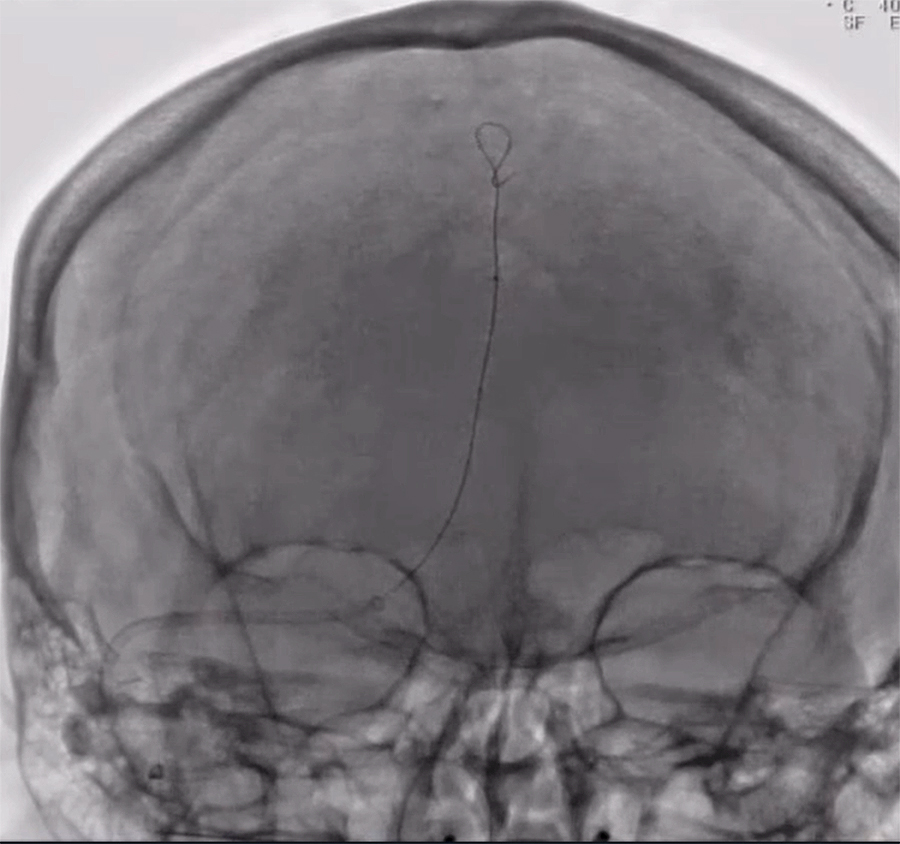

Image shows the catheter (skinny black line in the middle of the skull) a tube that was threaded through the patient’s femoral vein in her leg and up into her skull. The black line is the wire that guides the catheter to get up to the top of the head, in order to suck the clot out of the vein. Credit: UB Neurosurgery